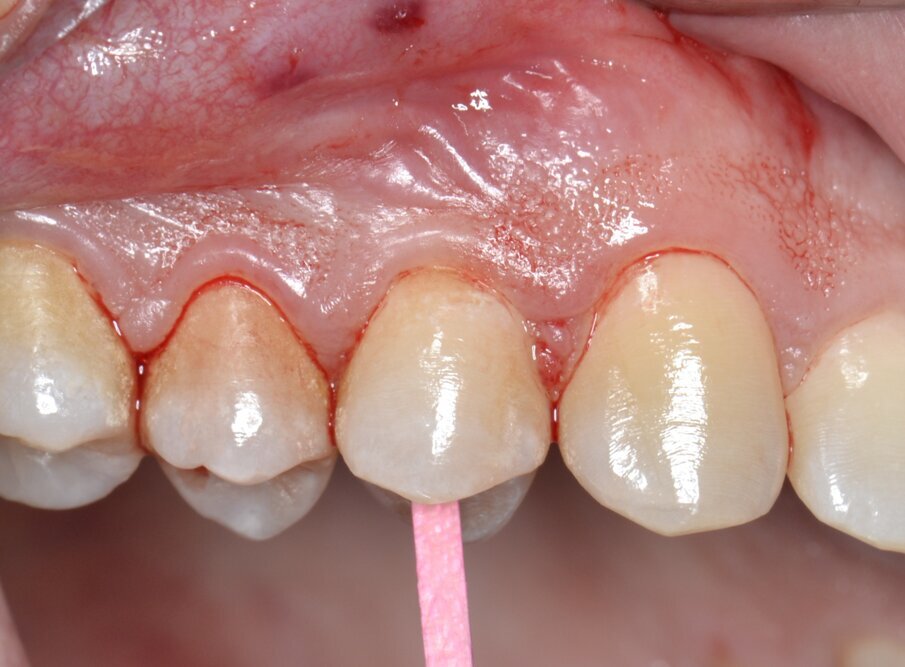

Il primo follow-up effettuato a 14 giorni mostra un eccellente stato di salute dei tessuti duri e molli; è importante sottolineare come il profilo di emergenza della protesi provvisoria, opportunamente lucidato al momento della protesizzazione, guiderà i tessuti molli durante tutto il periodo di guarigione (Fig. 19). Le immagini del secondo follow-up a 4 mesi indicano una condizione di sostanziale salute e stabilità dei tessuti peri-implantari duri e molli: questo consente di programmare la successiva fase di finalizzazione protesica (Fig. 20).

Fig. 19 - Follow-up a 14 giorni.